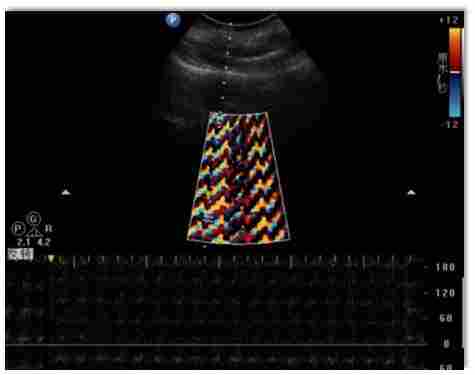

下面就用具体的图像来展示常见的一些干扰情况:

中远场彩色斑块状的干扰。

彩色取样框中等间距彩色折线状的干扰